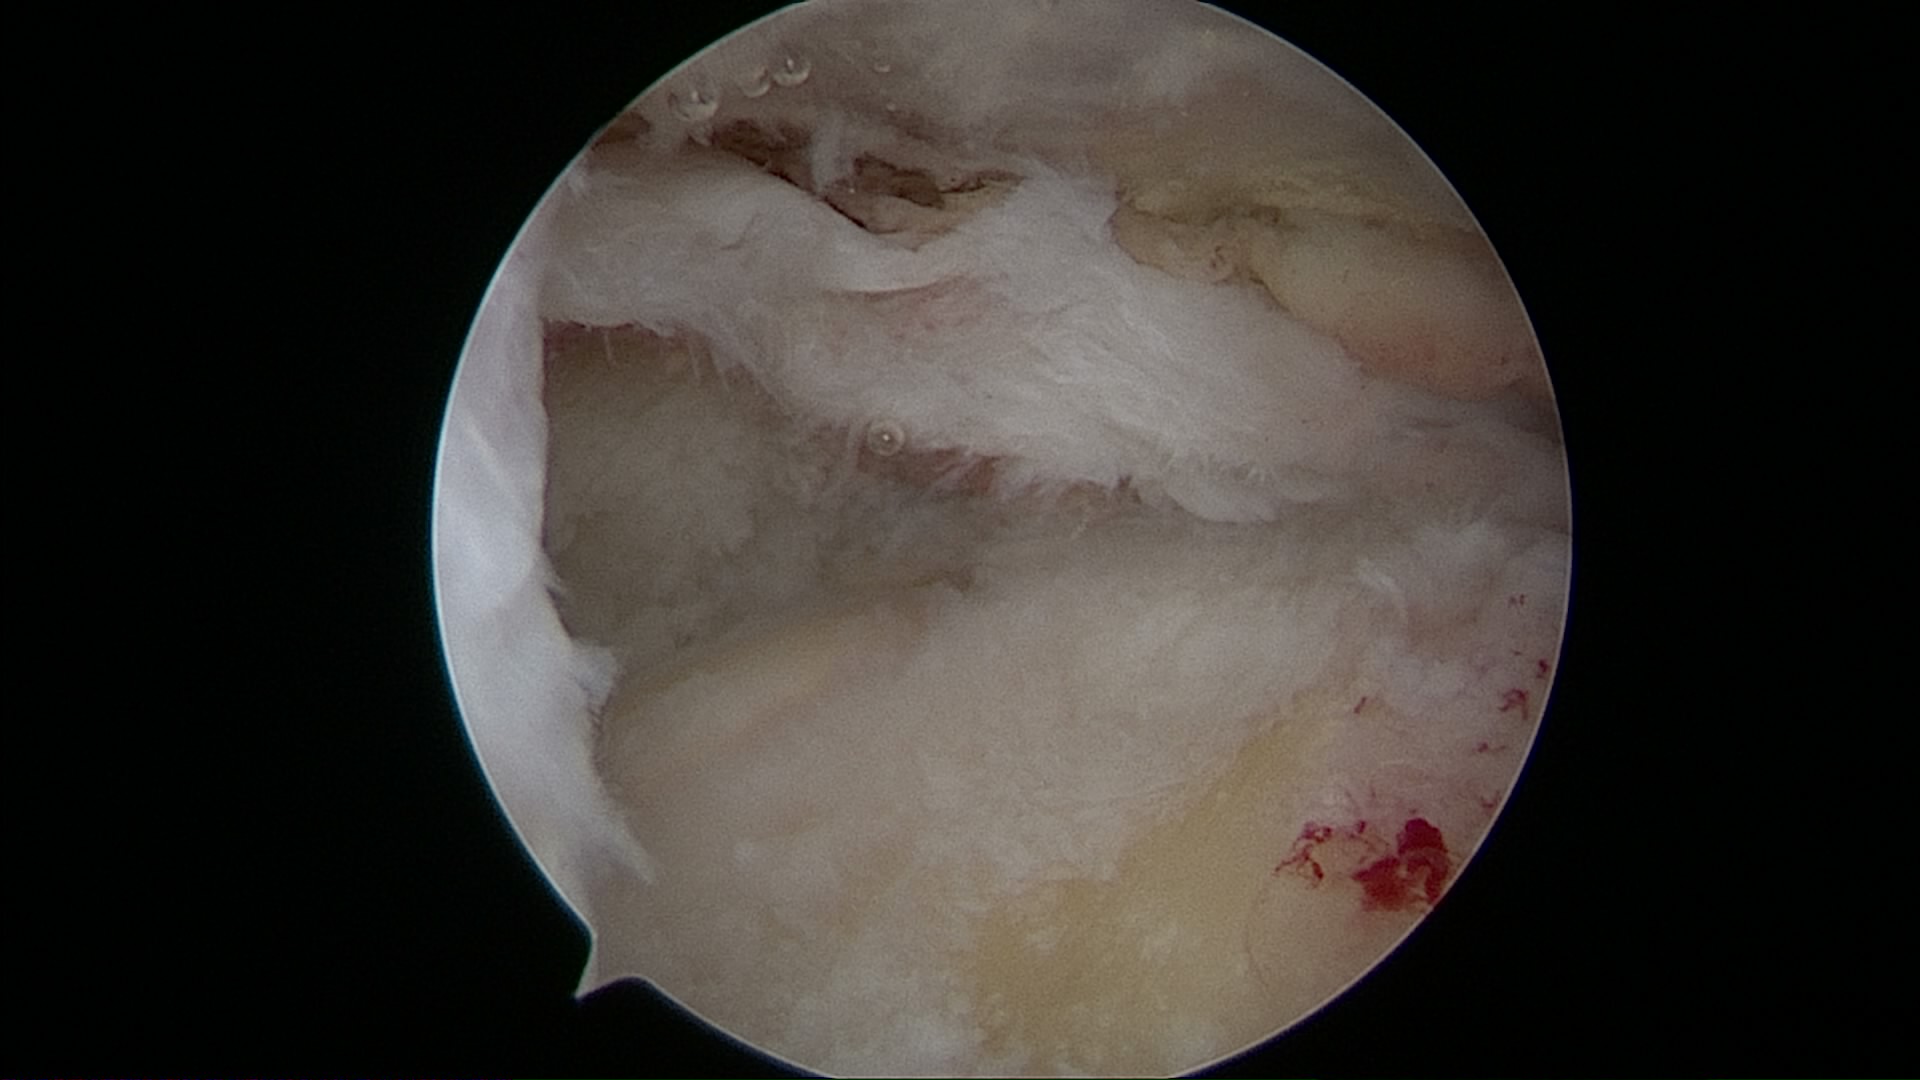

Lesión de Manguito Rotador

Reparación de Manguito Rotador con suturas y anclaje

Cirugía de reparación de manguito rotador con suturas y anclajes

Cirugía manguito rotador con suturas y anclajes